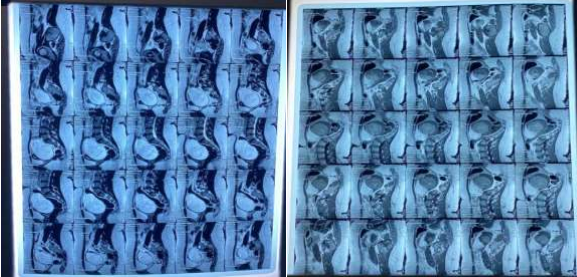

Pelvic ultrasound showed a left dermoid ovarian cyst. The abdominal MRI pelvis with contrast showed a mass lesion of about 12.5cm vertically, 11.5cm TS and 10cm in AP diameter in the cul de sac space, encapsulated in tough capsule and consist of fluid signals, soft tissue and fat signals with some tiny foci of very low signal intensity on all pulse sequences which may stand for calcification. All the serum tumor markers were normal.

Fig 1.1: Sagittal view

Fig 1: Preoperative abdominopelvic Magnetic resonance imaging with contrast demonstrating a mass lesion of about 12.5cm vertically ,11.5cm TS and 10cm in AP diameter in the cul de sac space, encapsulated in tough capsule; consist of fluid signals, soft tissue, fat signals and calcifications.